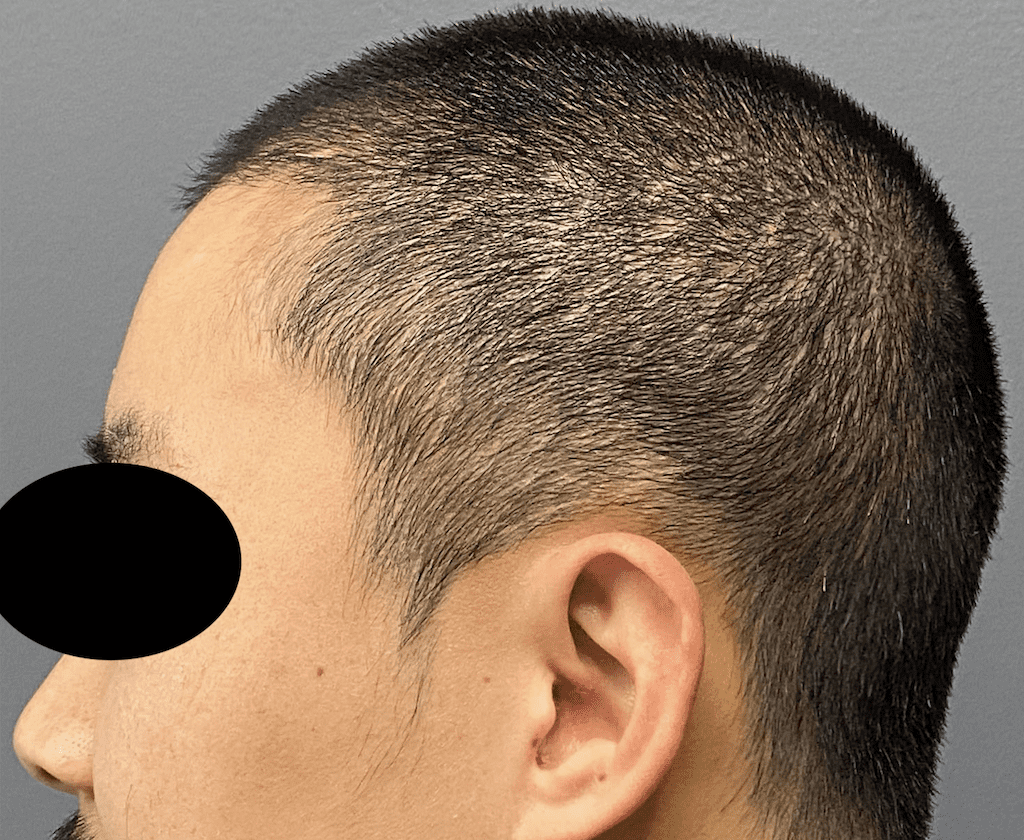

Patient 100

Desire for reshaping of an asymmetric flat back of the head in a shaved head male.

A combined back of the head reshaping procedure was done with a custom skull implant, sagittal ridge reduction and a right temporal muscle reduction.

Desire for reshaping of an asymmetric flat back of the head in a shaved head male.

A combined back of the head reshaping procedure was done with a custom skull implant, sagittal ridge reduction and a right temporal muscle reduction.